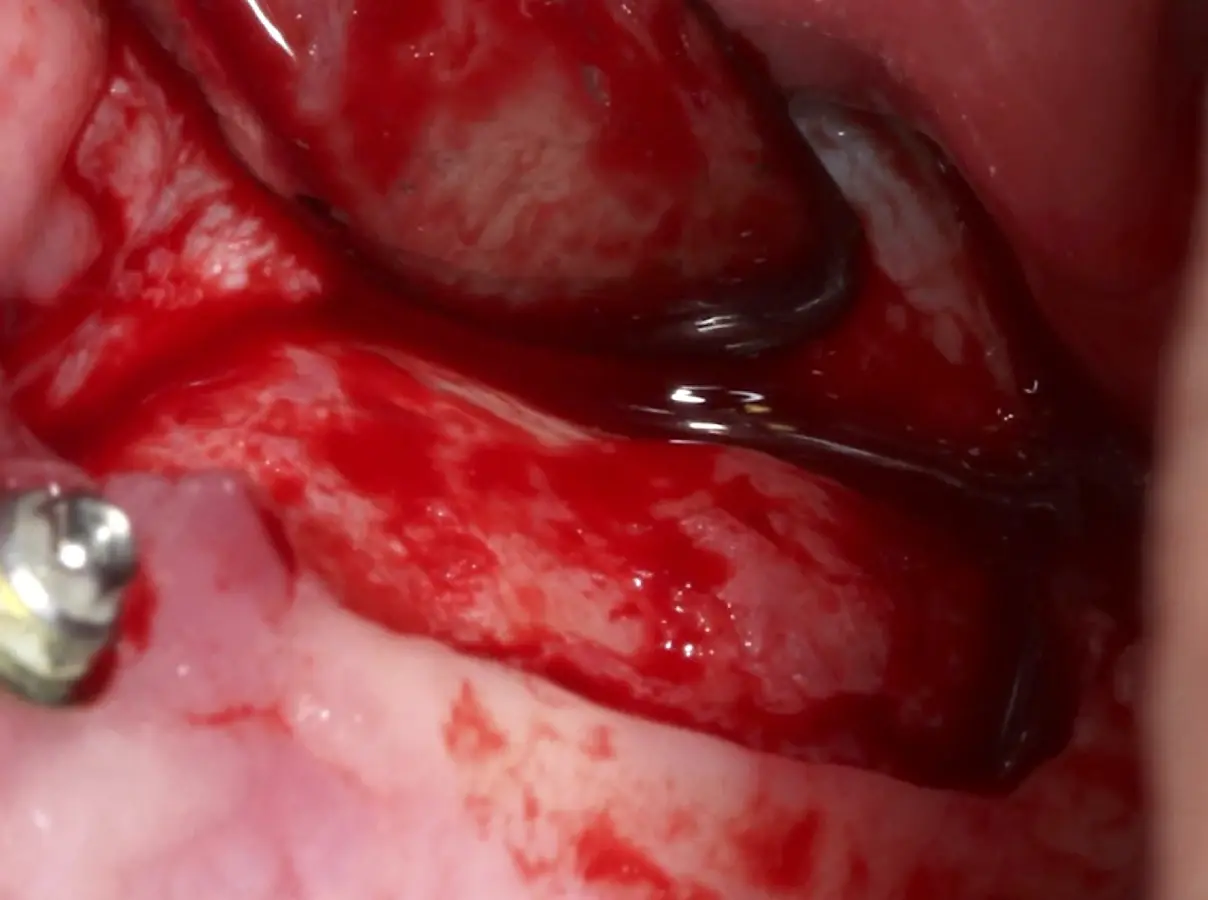

Figura 15. Incisión supracrestal y decolado a espesor total del lado izquierdo.

Figura 17. Inicio del desprendimiento de la membrana de Schneider con el inserto de presión hidráulica.

Figura 18. Elevación de la membrana de Schneider con curetas manuales (a, b).